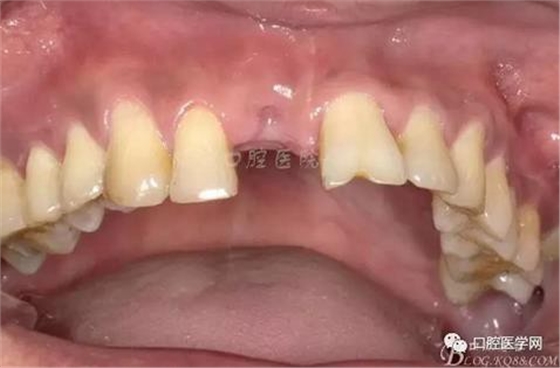

圖4 術前正位頜面照